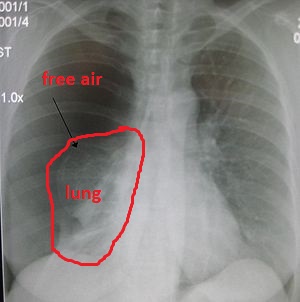

All of the air in your lungs is supposed to be contained within the spongy tissue of the lung. If air leaks out of the lungs and begins to fill up the space between the lungs and the inside of the chest, it’s referred to as a “pneumothorax,” shown in this image:

The chest on the left side of the image looks much darker than the the right side because it’s full of pure air, instead of lung tissue plus air. Here I’ve outlined the collapsed lung in red, and labeled the free air:

This is very bad because the collapsed lung isn’t functioning at all — it’s not delivering any oxygen to the body. Luckily, there is still one functioning lung, but it’s important to fix the collapsed lung and help it inflate again.